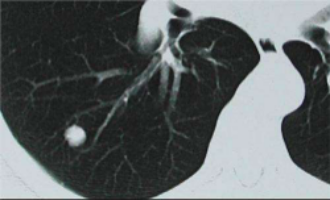

中心瞄准于医学人工智能,重点研究医学知识图谱和影像组学两个方向。目前在影像组学方向上研发的产品主要有宫颈癌检测分析系统、肺结节检测分析系统、骨龄检测分析系统、胃癌病理检测分析系统和眼底影像智能诊断系统。

肺小结节辅助诊断系统:在天池医疗肺结节比赛中,团队在第一季获得肺部结节智能诊断第九名的好成绩。目前,本项目已经设计了一个肺结节检测可视化程序,将检测系统的结果直接标记在CT影像中。